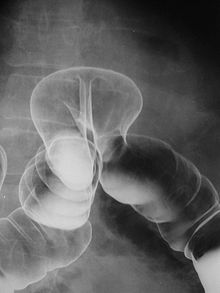

Внутренняя грыжа, визуализируемая при ирригоскопии

Ирригоскопия (лат. irrigare — орошать + др.-греч. σκοπέω — наблюдаю, исследую) — рентгенологическое исследование толстой кишки с ретроградным введением в неё рентгеноконтрастного препарата. В ходе исследования выполняются рентгеновские снимки (ирригограммы).

В прямую кишку пациента вводится наконечник клизмы, заполненной контрастным препаратом (чаще всего бариевой взвесью), после чего под контролем рентгеноскопии начинается заполнение толстого кишечника. Производятся обзорные и прицельные снимки в различных положениях пациента. Далее, после опорожнения кишечника, изучается рельеф его слизистой. В дальнейшем возможно заполнение толстой кишки воздухом («двойное контрастирование») с помощью аппарата Боброва для более детальной визуализации[1].

Ирригоскопия обычно применяется для оценки состояния толстой кишки. С помощью ирригоскопии можно диагностировать и оценить степень изменений при язвенном колите и болезни Крона, визуализировать опухоли толстой кишки, свищи, дивертикулы и пороки развития. Ирригоскопия — метод, позволяющий оценить расположение и размеры толстой кишки, а также её функциональные особенности.